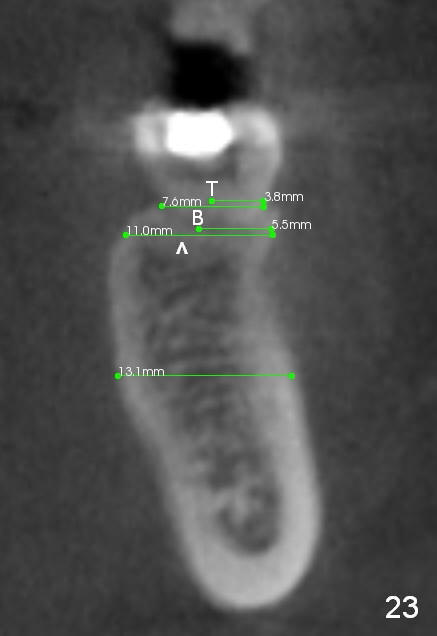

CBCT taken 15 months post cementation shows that the implant is buccally placed (Fig.21 B), associated with possible postop buccal plate resorption (as compared to Fig.23 (coronal section of the site of #19). The buccal plate is not only thinner than the lingual one, but also concave (Fig.22 <). The tooth center (i.e., septum; Fig.23 T) is more buccally located than the center of the basal bone (B). Considering the denser bone lingually, the initial osteotomy should be more lingually (^). If the implant develops infection, it will be replaced by a more lingually placed implant (Fig.24 green).